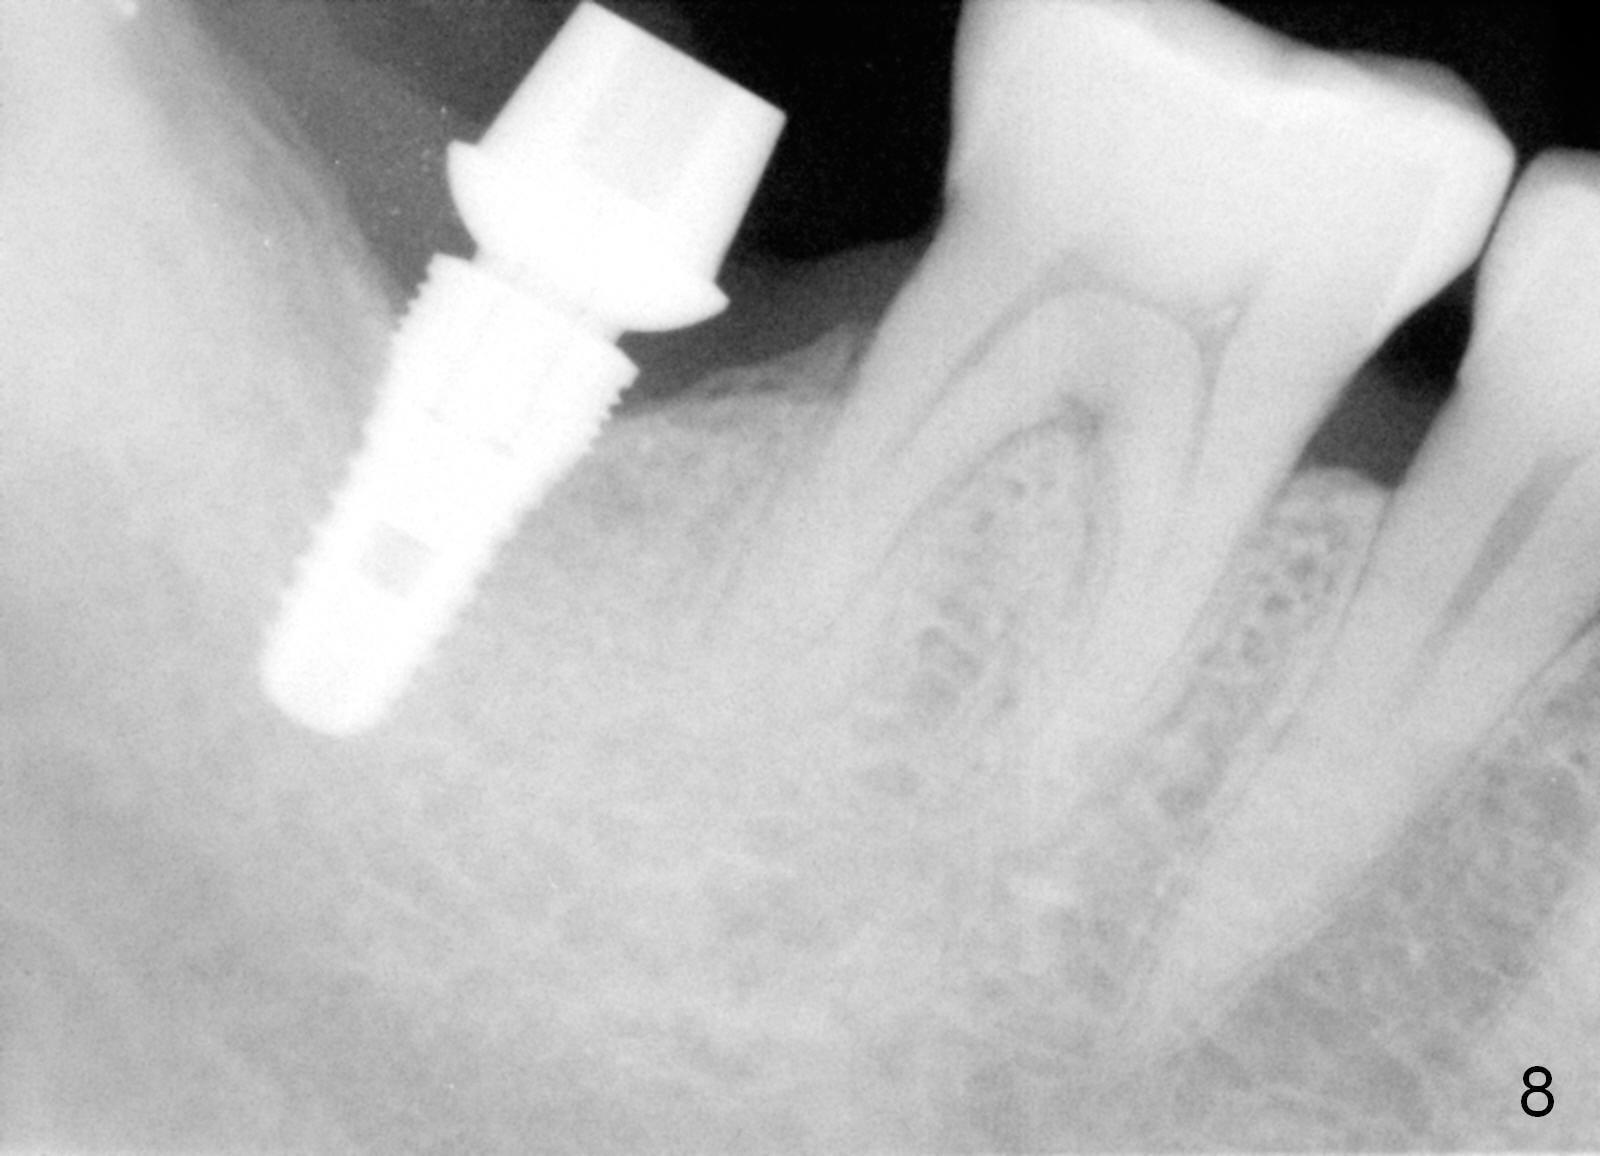

There appears to be bone loss coronally 15 months postop (Fig.8). There is no bone loss 1 year post cementation (2 years 3 months postop, Fig.9). If the implant were longer, it might perforate the lingual (L) plate (Fig.10 (1.5 years post cementation)).